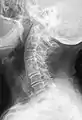

Short ribs at the first lumbar vertebra, which is thus a transitional vertebra, since lumbar vertebrae normally do not have ribs attached to them.

Transitional vertebrae have the characteristics of two types of vertebra. The condition usually involves the vertebral arch or transverse processes. It occurs at the cervicothoracic, thoracolumbar, or lumbosacral junction. For instance, the transverse process of the last cervical vertebra may resemble a rib. A transitional vertebra at the lumbosacral junction can cause arthritis, disk changes, or thecal sac compression. Back pain associated with lumbosacral transitional vertebrae (LSTV) is known as Bertolotti's syndrome. One study found that male German Shepherd Dogs with a lumbosacral transitional vertebra are at greater risk for cauda equina syndrome, which can cause rear limb weakness and incontinence.[10]